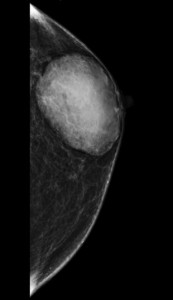

El método de elección es mamografía bilateral, puesto que esta prueba es la requerida en casos de varones adultos con sintomatología no aclarada clínicamente (en jóvenes y adolescentes su indicación es excepcional). Es imprescindible en el diagnóstico de la patología mamaria.

Haz click en las imágenes para verlas ampliadas